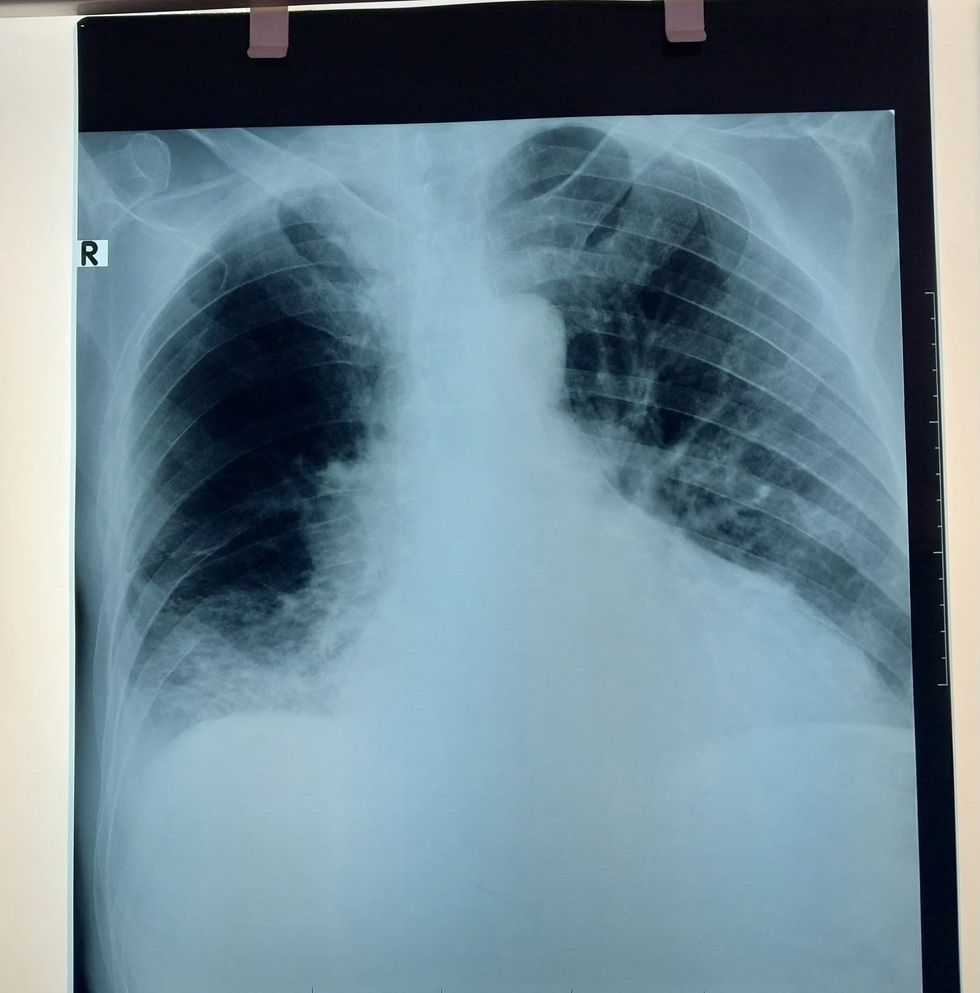

“Derisa dikush humb kohë për të gjetur një pamje të keqe në ‘Univers’ ne merremi me shërbime për qytetarin. Para 3 viteve është dashur të pritet me javë për një fotografim në qendër, kurse tani ky realizohet kudo që ka nevojë. Pamje nga një fotografim në shtëpi me rëntgenin mobil që dikur ‘lironte’ rrezatim”.